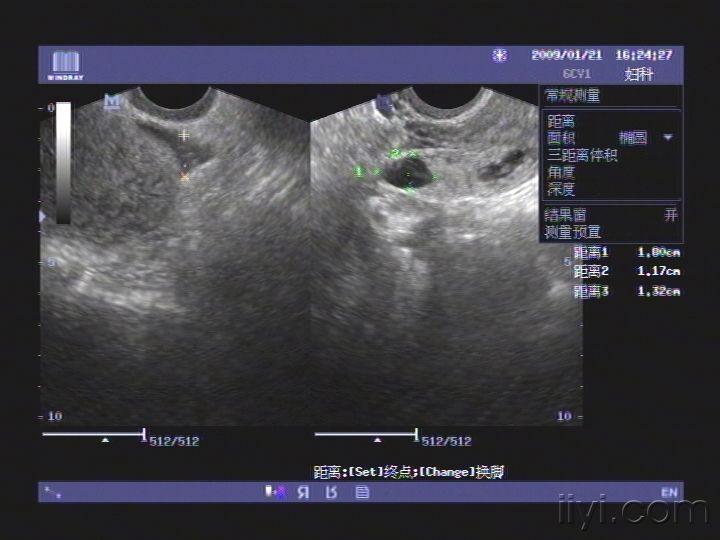

一例宫内孕合并宫外孕的彩超

你帮我看看这彩超图片啥意思?是宫外孕么?我现在孕六周多几天!